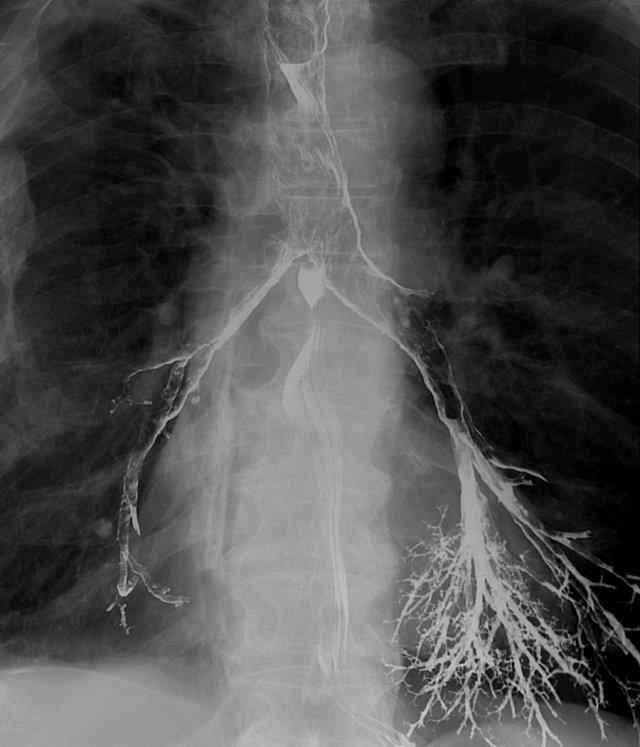

Thăm khám thực quản

Luôn theo dõi quá trình di chuyển của barium qua thực quản cho đến khi vào dạ dày.

Các rối loạn tại vùng nối thực quản-dạ dày thường được bệnh nhân cảm nhận như một vấn đề ở vùng họng.

Lý giải cho điều này là ở những bệnh nhân có tắc nghẽn đoạn xa, trào ngược dạ dày-thực quản hoặc rối loạn vận động, cơ nhẫn hầu phải hoạt động rất mạnh để ngăn thức ăn trào ngược lại vào hầu họng — kèm theo nguy cơ hít sặc.

Trương lực cơ tăng cao này tạo cho bệnh nhân cảm giác có vật gì đó trong cổ họng.

Các hình ảnh là của một bệnh nhân có cảm giác vướng họng (globus sensation).

Nguyên nhân là do trào ngược nặng và tình trạng tăng trương lực cơ nhẫn hầu thứ phát.

Thoát vị cạnh thực quản lớn kèm trào ngược là nguyên nhân gây ra các triệu chứng.

Hình ảnh tối ưu của vùng nối dạ dày-thực quản khi khí trào ngược từ dạ dày vào thực quản đã được phủ thuốc cản quang ở bệnh nhân thoát vị hoành trượt.

Có thể đạt được hình ảnh xuất sắc của vùng nối dạ dày-thực quản bằng cách thực hiện các bước sau:

- Yêu cầu bệnh nhân uống viên sủi zoru-granules (hoặc coca cola) để tạo đầy hơi tối ưu trong dạ dày.

- Dặn bệnh nhân không ợ hơi, mà giữ hơi trong dạ dày cho đến thời điểm nuốt.

- Đặt bệnh nhân ở tư thế chếch trước-trái (left anterior oblique).

- Nâng mặt bàn lên 45 độ.

- Nuốt barium tỷ trọng cao để phủ thực quản tối ưu.

- Chụp hình ảnh khi khí trào ngược từ dạ dày vào thực quản đã được phủ barium.